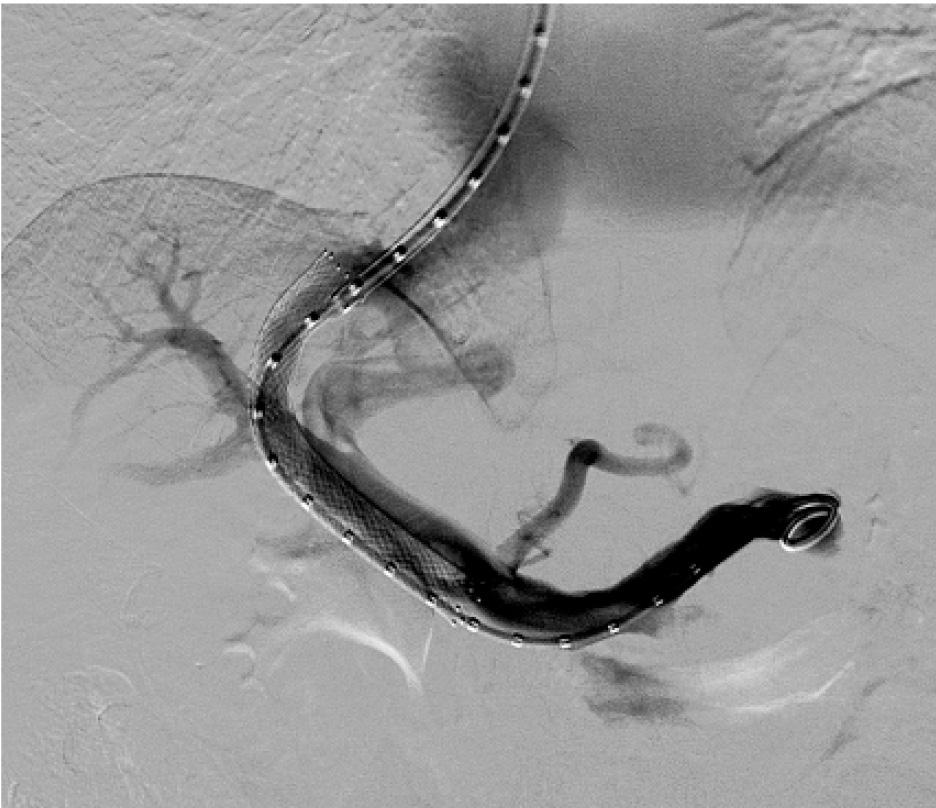

Рис. 1. Контрольная портография после выполнения TIPS

В клиниках общей хирургии и госпитальной хирургии ВМедА больной выполнены 2 операции криосорбции, ультрафильтрации и реинфузии асцитической жидкости, 2 сеанса эндоскопического лигирования вен пищевода. С целью коррекции тромбоцитопении пациентке 12.02.2008 г. произведена эмболизация селезеночной артерии с положительным эффектом. Уровень тромбоцитов в периферической крови повысился с 25–40 × 109/л до 75–100 × 109/л. Однако асцитический синдром у больной не купировался. Решением консилиума традиционные шунтирующие операции у пациентки признаны невозможными в связи с декомпенсацией цирроза печени и наличием гигантской опухоли брюшной полости и малого таза (более 20 см в диаметре). В то же время оперативное лечение по поводу опухоли было связано с высоким риском в связи с наличием диуретикорезистентного асцита, выраженного варикозного расширения вен пищевода, печеночной недостаточности. Кроме того, больной было отказано в постановке на лист ожидания трансплантации печени из-за наличия опухоли. Учитывая рецидивирующее течение диуретикорезистентного асцита, высокий риск рецидива пищеводных кровотечений, пациентке 05.03.2008 г. выполнено трансъюгулярное интрапеченочное портосистемное шунтирование (TIPS) под местной анестезией (рис. 1).

Особенностью оперативного вмешательства было проведение транспеченочной пункции воротной вены при смещенной печени (за счет опухоли больших размеров). Кроме того, у пациентки отмечены выраженная деформация и смещение верхней брыжеечной вены, ствола воротной вены. После установки стента произошло снижение портального давления с 550 до 280 мм вод. ст. Послеоперационный период протекал без осложнений. У пациентки отмечено купирование диуретикорезистентного асцита. Варикозное расширение вен пищевода снизилось до 1–2 ст.